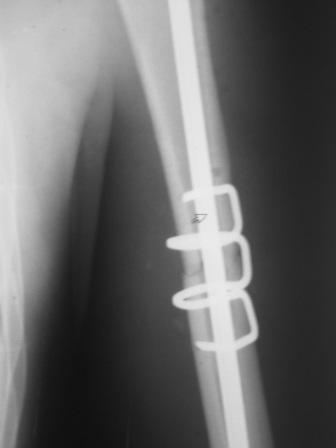

Всё правильно, просто я несколько разрозненно пытался сказать на частных примерах, то , что Вы систематизировали. Совершенно верно данный перелом можно и так и эдак, наиболее оптимально антеградное штифтование, хотя я бы предпочёл пластину LCP(просто - ну лучше у меня это получается и всё, а больному не вредит тот же функциональный способ). А низковато для неблокированного штифтования с конструкциями с термомеханической памятью, то, что представленно на втором снимке.